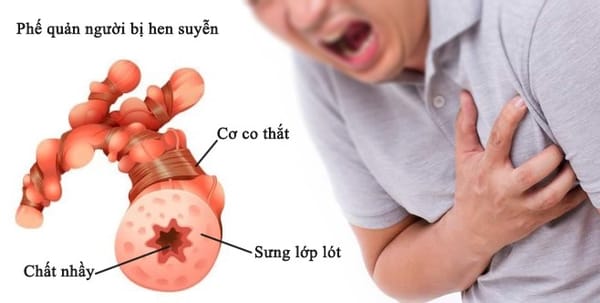

SKĐS - Do nhạy cảm với môi trường, nên khi thời tiết thay đổi đột ngột, nóng lạnh thất thường, bệnh nhân hen phế quản dễ lên cơn hen cấp, rất nguy hiểm nếu không xử trí kịp thời. Hen phế quản còn gọi là hen suyễn là tình trạng